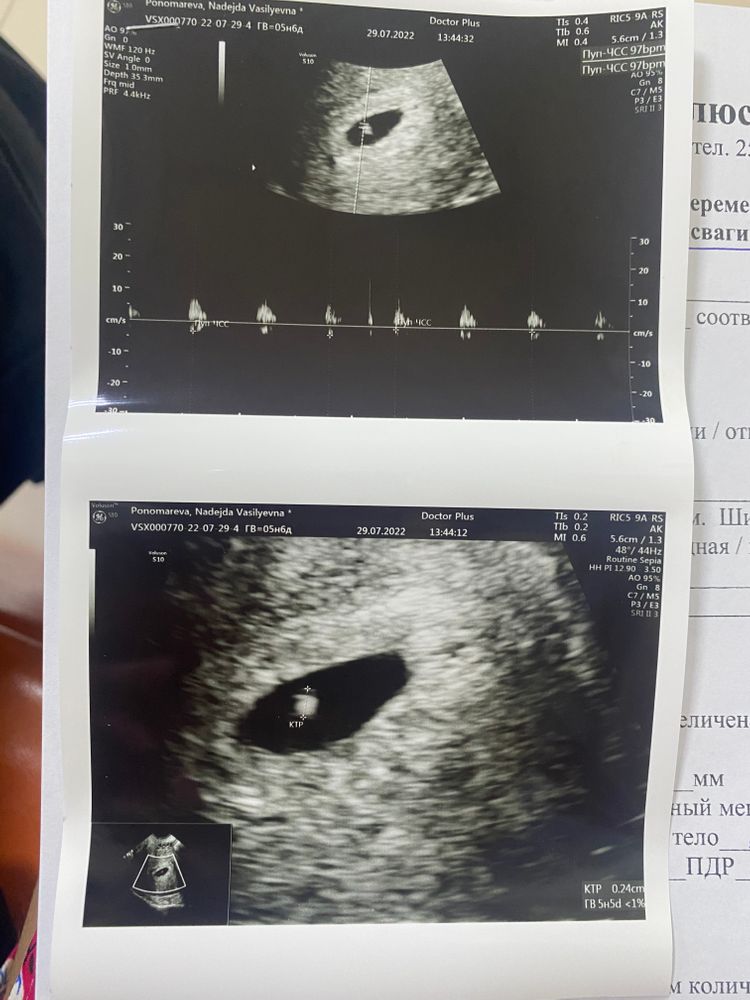

6.07.2022 состоялся криоперенос 2х пятидневок 4АА и 3ВВ в клинике Ава Петер🤞🏽🤞🏽🤞🏽